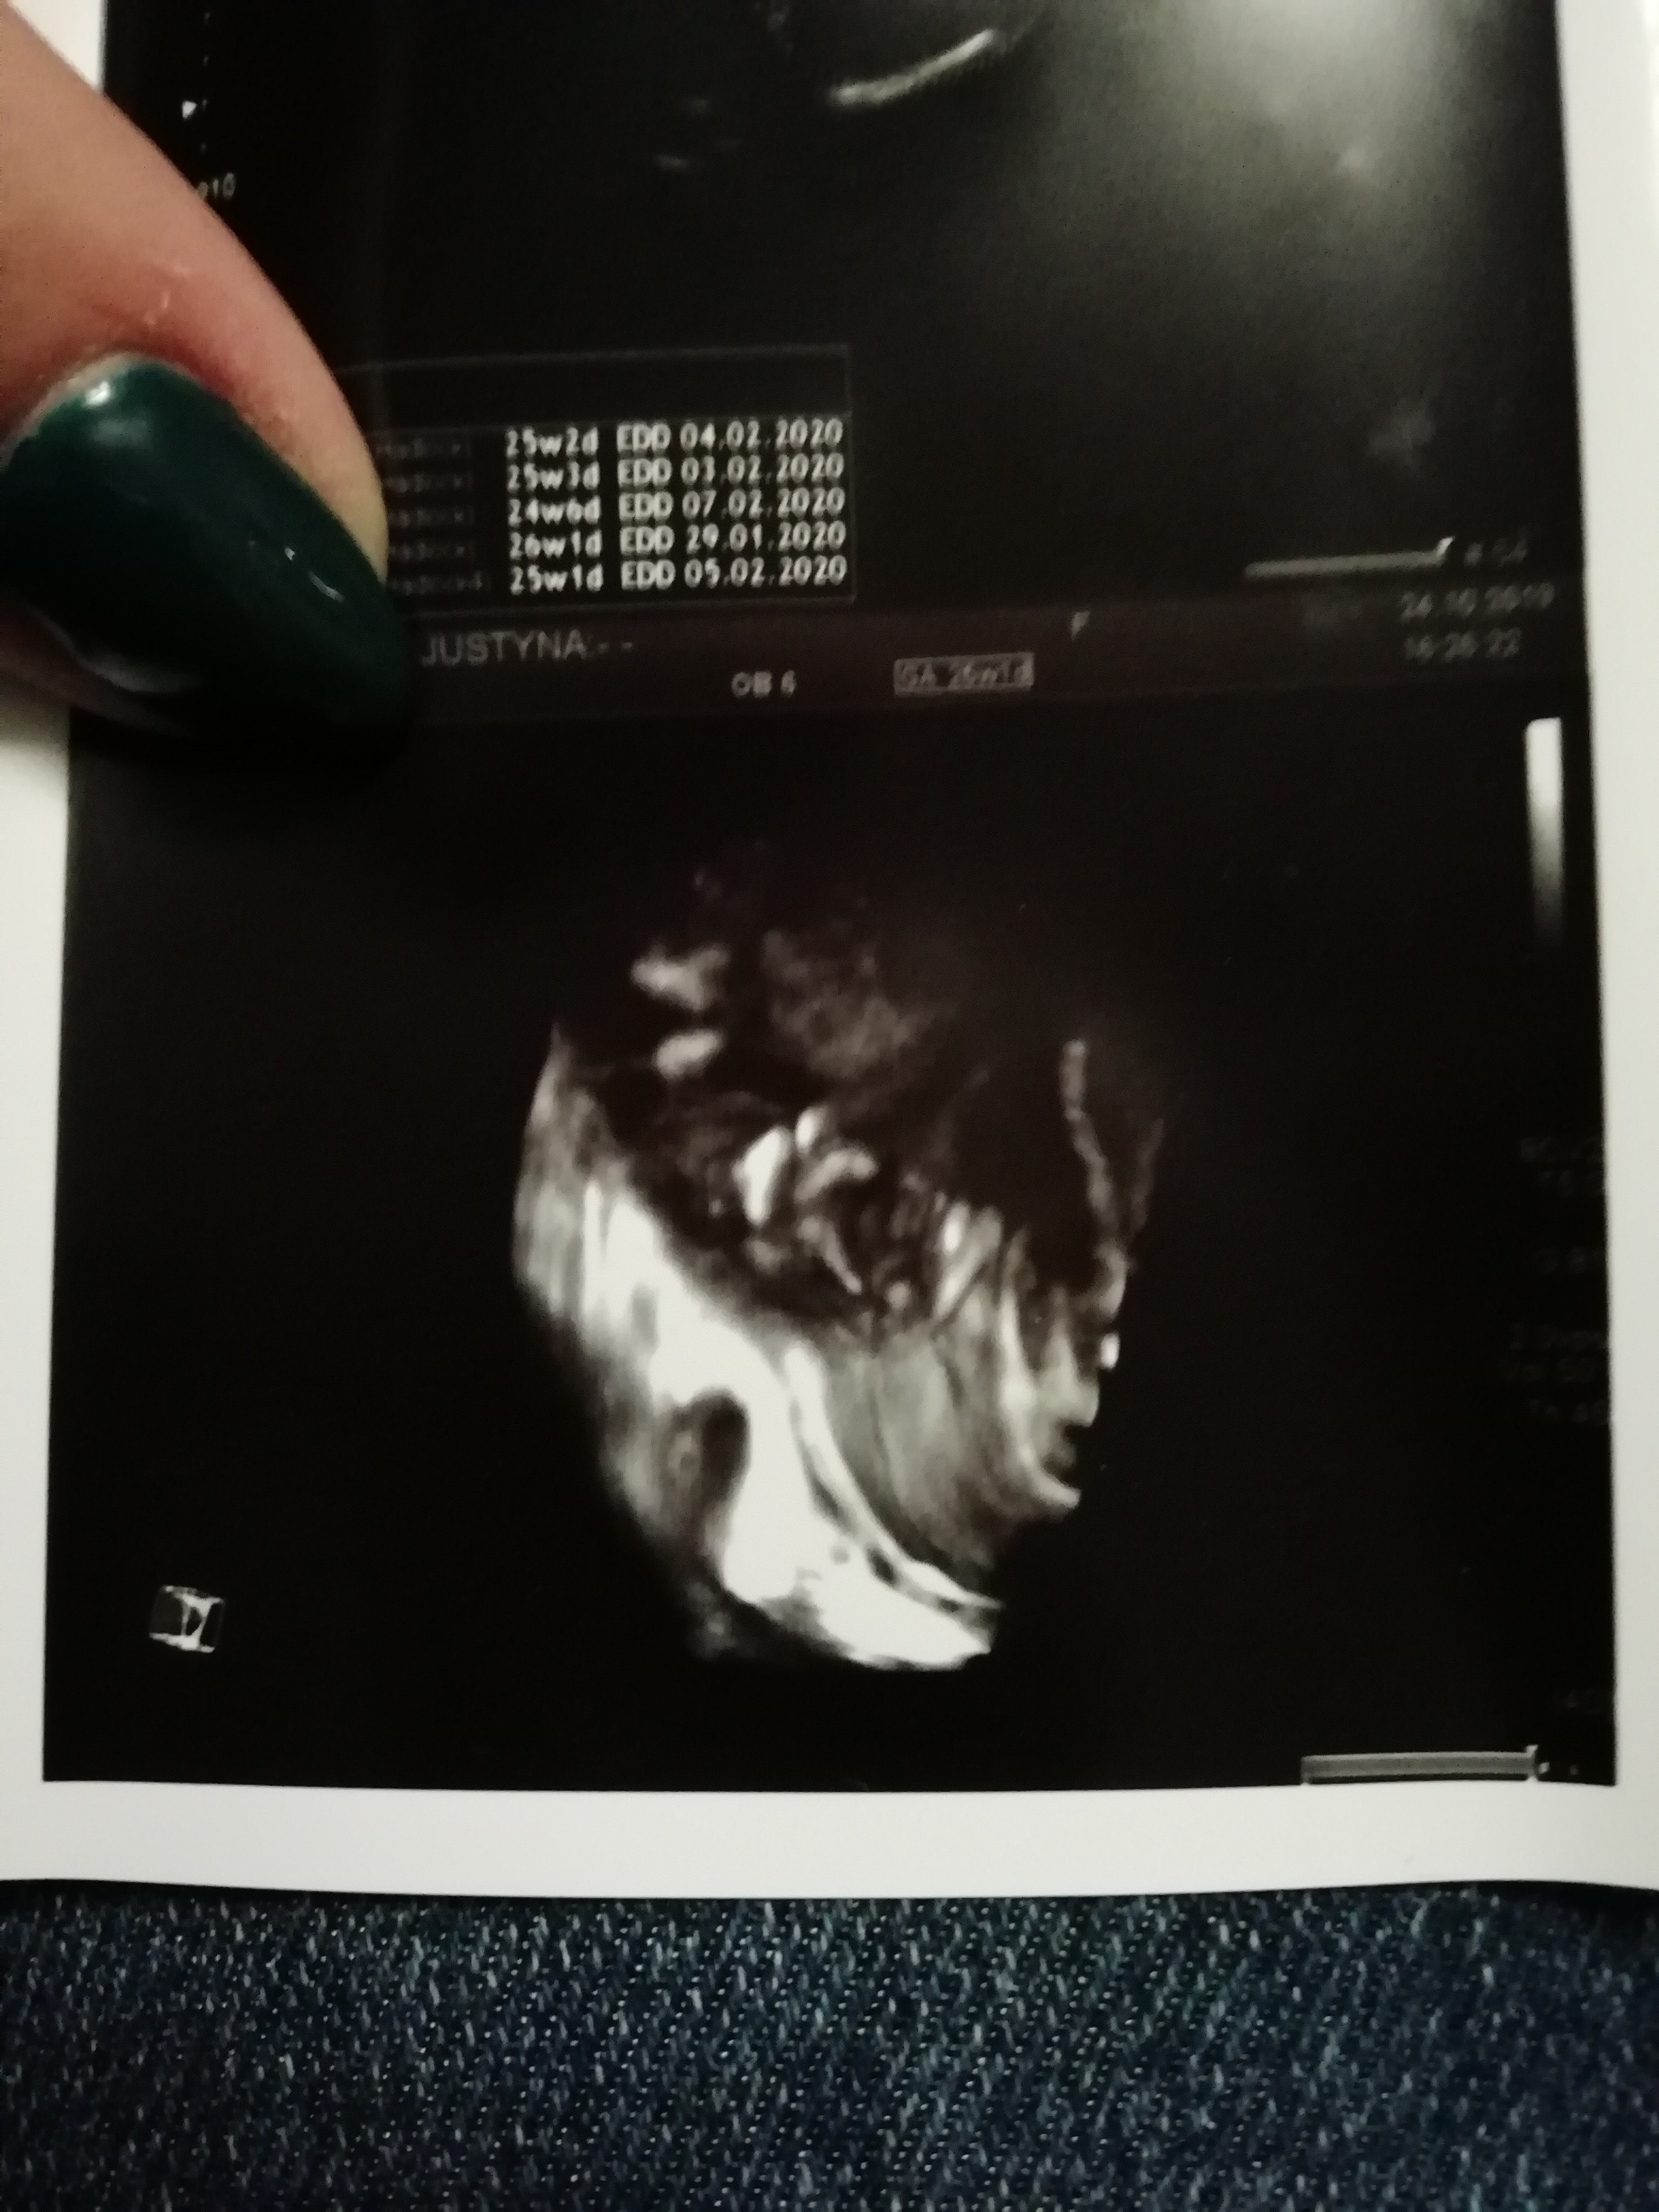

A tu jeszczw nochalek raz :)

IMG_20191024_205527.jpg

Zobacz załącznik 1037658